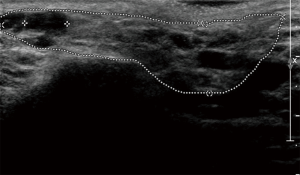

The principal ecostructural abnormalities detectable by SGUS are the following: parenchymal non-homogeneity, hypo-anechoic or hyperchoic areas (due respectively to cysts or calcifications), size variations, irregularities in glandular profiles and the presence of intra- or periglandular lymph nodes (19) (Figures 3-5). As highlighted by several authors (9,20), the most relevant SGUS alteration of pSS is the parenchymal inhomogeneity detectable bilaterally. This ultrasound finding, is the one that has shown the greatest agreement with the alterations documented with the scintigraphy of the salivary glands, sialography, and minor labial salivary gland biopsy (LSGB) (21,22). At the level of the parotid and submandibular glands, SGUS shows the best relationship of sensitivity to specificity, with a positive predictive value of 72.0% and a negative predictive value of 96.0% (23). Compared to contrast sialography and to salivary gland scintigraphy, SGUS showed higher sensitivity (75.3%, 72.7% and 70.1%, respectively), with similar specificity (83.5%, 84.9% and 82.3%, respectively) (7). Ultrasound findings of hypoechoic, multiple, circumscribed or confluent areas and/or multiple cysts correspond to a histological pattern of ductal ectasia surrounded by lymphocyte infiltrate or dilated glandular lobes surrounded by lymphocyte aggregates. In particular, Kawamura et al. (24) and Salaffi et al. (7,12) demonstrated that the anomalies documented at SGUS are strongly related to histological changes (12), and that the SGUS score proposed for classification is well correlated with sialographic classifications (12). Cornec et al. (15) have verified that morphological abnormalities of the salivary glands can be detected early in the course of pSS. The diagnostic characteristics of the SGUS also seem not to vary during the disease. Applying an ultrasound cut-off of 5, the proposed SGUS scoring system was slightly less specific (85.7% vs. 77.9%) but more sensitive (94.9% vs. 98.7%) compared to the AECG criteria (4,13).